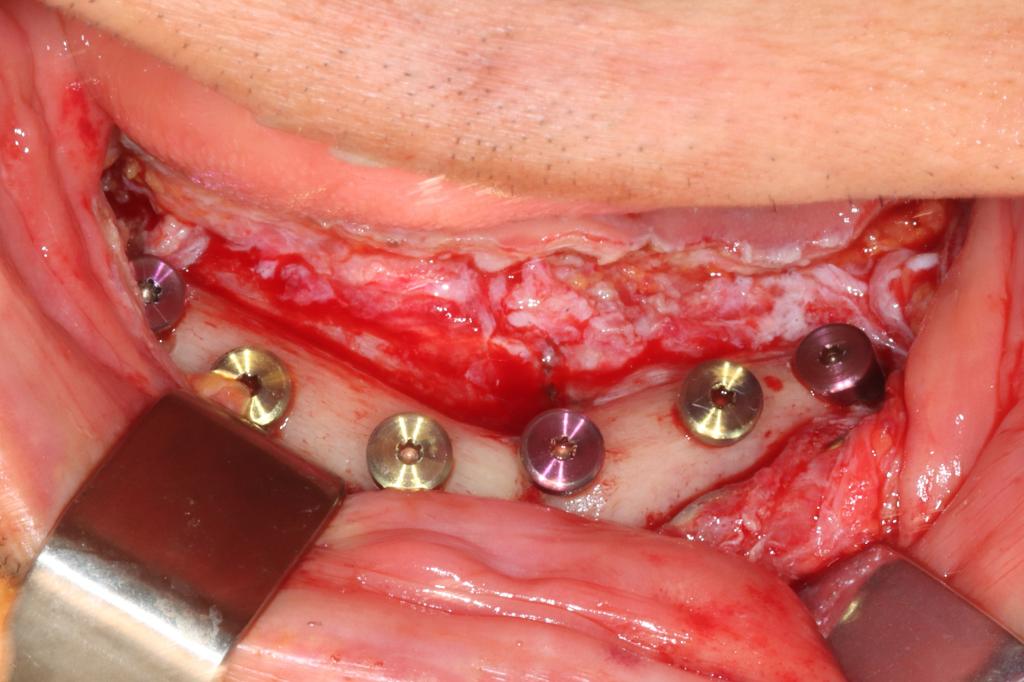

术后口内照

在手术中,李奇副主任医师顺利在患者颅骨外固定手术标记物,拍摄螺旋CT后确认固定标志物的钉子穿透颅骨第一层骨皮质到达第二层骨髓腔,位置精准。麻醉科王智主任在患者清醒状态下进行了经鼻纤支镜麻醉,仅用时不到15秒一次成功,保证患者插管时血压和心率平稳。随后,将术前CT、术前规划、患者颅颌骨位置及机器人机械臂进行配准标定。杜良智主任团队通过机器人亚毫米级的定位方式,精准控制避开固定腓骨的钛板和钛钉,用时三小时,顺利将6颗种植体植入规划位置,确保种植体按预设位置准确就位,为后期修复上颌缺失牙列打下基础。